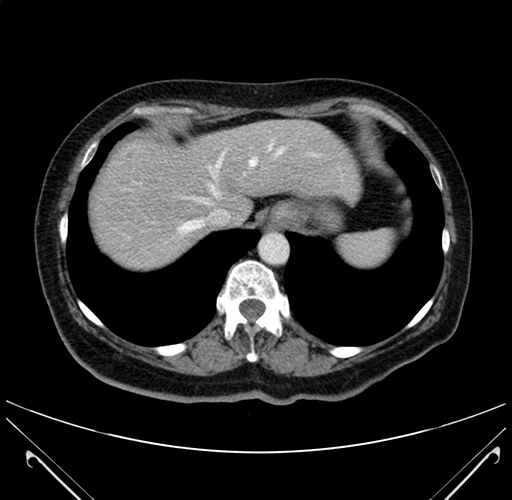

Pre-Chemo: Axial Venous

Axial Venous